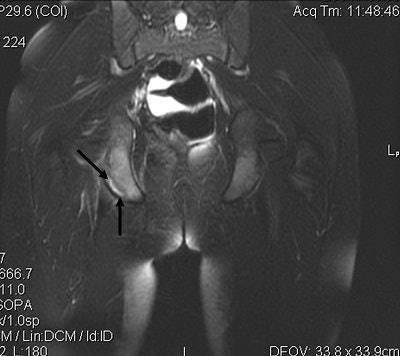

Plain radiographs, including an anteroposterior view of the pelvis, showed an avulsion of the right ischial tuberosity in the typical inferolateral location. An MR exam demonstrated osseous and soft-tissue edema, along with an avulsion fracture of the right ischial tuberosity (Figures 1-4).

| Figure 3. Coronal T2-weighted MR image of the pelvis demonstrates increased signal intensity at the avulsion site on the right ischial tuberosity (black arrows). |